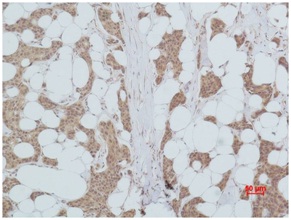

Immunohistochemical analysis of paraffin-embedded human Breast caricnoma using PI3 Kinase P85α(BE3377)Rabbit pAb diluted at 1:500.